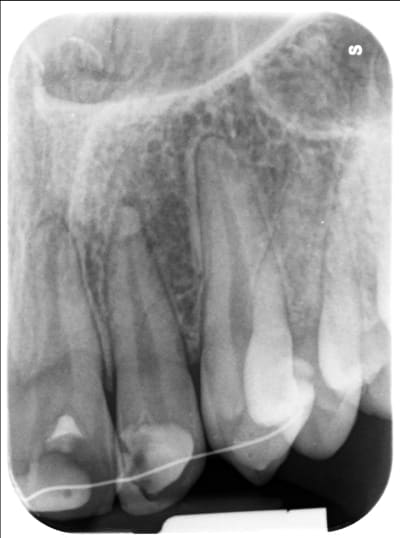

Jeune patient de 18 ans, qui a fait une chute en juin 2018 avec fracture coronaire de 22. J'ai suspecté une fracture du 1/3 apical de la racine. Dent vivante, contention souple 4 semaines.

Ce jour, légère sensibilité, la dent répond au froid, et à la radio l'apex a disparu.